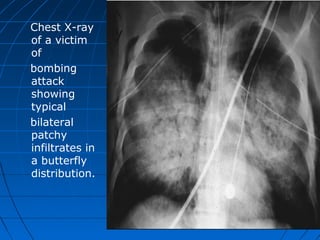

Chest X-ray

of a victim

of

bombing

attack

showing

typical

bilateral

patchy

infiltrates in

a butterfly

distribution.

 • Chest radiography is necessary for

anyone who is exposed to a blast.

 A characteristic “butterfly” pattern may be

revealed upon x-ray.

““Blast Lung”Blast Lung”

White Butterfly SignWhite Butterfly Sign

Chest X-ray of avictim of bombing attack showing typical bilateral patchy infiltrates in a butterfly distribution.

BLI’s ManagementBLI’s Management Diagnostic Evaluation  • Chest radiography is necessary for anyone who is exposed to a blast.  A characteristic “butterfly” pattern may be revealed upon x-ray.  • Arterial blood gases, computerized tomography, and doppler  technology may be used.  • Most laboratory and diagnostic testing can be conducted

““Blast Lung”Blast Lung” WhiteButterfly SignWhite Butterfly Sign